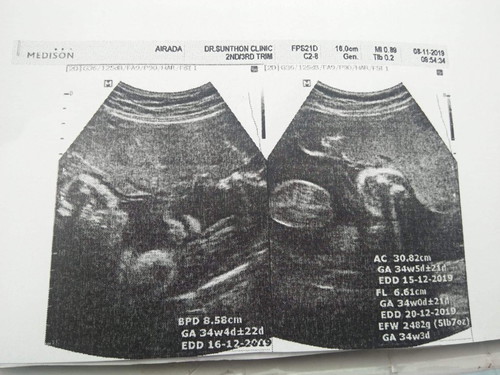

เมื่อวานไปหาคุณหมอตามนัดมา ซาวด์ดูน้อง คุณหมอบอกน้องน้ำหนักประมาณ 2500 (เค้าจะประเมินจากเครื่องซาวด์ ส่วนในเครื่องซาวด์ 2482 เพราะในเครื่องซาวด์34วีคแต่จริงๆ 36 วีคแล้ว น้ำหนักน้องจริงๆจะเยอะกว่าที่เครื่องซาวด์กับที่คุณหมอบอกใช่ไหมคะ กลัวน้องจะน้ำหนักน้อยไม่แข็งแรง